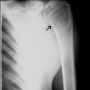

Daha nadir olarak görülen büyük bir osteoid osteomadır. En sık omurganın arka bölümünde ve uzun kemiklerin metafizinde ortaya çıkar. Ortadaki litik bölüm osteoid osteomada görülenden çok daha büyüktür ve etrafındaki skleroz çok daha incedir. İçindeki doku, osteoid osteomaya göre daha agresiftir. Omurgadaki ağrılı lezyonlar deformitelere (omurga eğriliğine) neden olabilirler. Tedavi bu bölgenin küretajı, tur aleti ile kazınması ve kemik dokusu ile doldurulmasıdır.